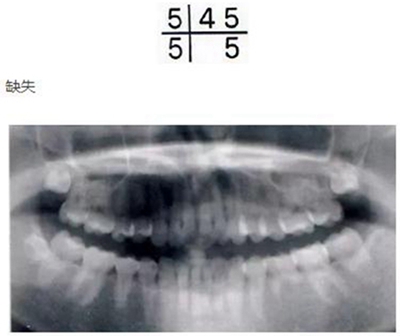

乳牙的晚期殘存(恒牙的先天性缺失)

[原因不明的多顆恒牙先天性缺失病例(17歲)]右下E殘存,

2.jpg

因為乳牙并不是搖搖欲墜的狀態(tài),所以最好讓醫(yī)生檢查下牙齦下面有沒有恒牙。

解說 確認是否是恒牙的先天性缺失

乳牙的晚期殘存有可能是恒牙的先天性缺失引起的。恒牙的先天性缺失有1、2顆牙缺失,也有好幾顆牙同時缺失的情況。數(shù)顆恒牙的缺失有可能是特定的先天性疾病(外胚層發(fā)育不良綜合征*1、色素失禁癥*2)引起的,需要加以注意。

好發(fā)部位位于第三后磨牙、上頜側(cè)切牙、上下頜第二前磨牙。根據(jù)有關(guān)研究,切牙從上頜遠中側(cè)和下頜近中側(cè)開始退化。磨牙無論上下頜都是從遠中側(cè)開始退化,有一定的規(guī)律。

缺失部分有空隙的話,可以用殘存齒進行修補,但是根據(jù)上下頜關(guān)系也有不能采用這種方式病例。如果僅靠正畸治療無法解決問題的話,將來有可能在缺損部植入修復(fù)物和假牙,因此需要事先告知父母讓其有心理準備。

另外,先天性缺失是有遺傳性的,如果哥哥發(fā)現(xiàn)有缺失情況,那么弟弟也有可能缺失,因此最好也帶到醫(yī)院檢查一下比較好。